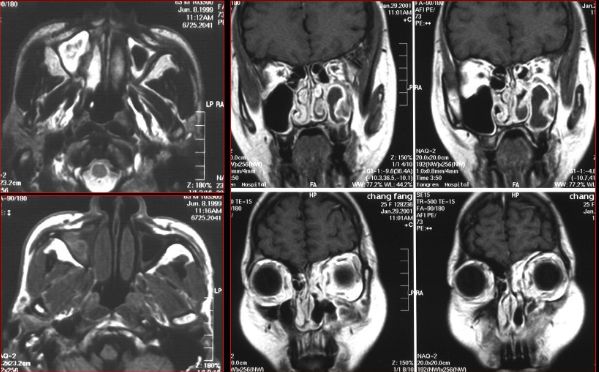

蝶窦炎—眶尖综合症

鼻窦炎—眶尖综合症